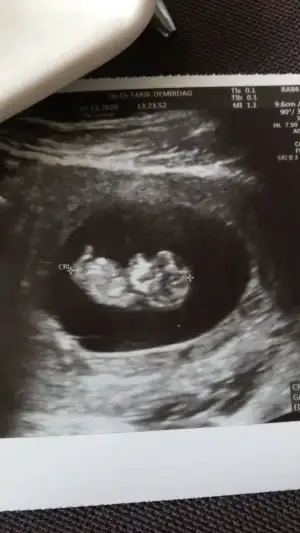

dr soylemeden siz gorun genital nub teorisi ( bebegin cinsiyeti)

Erkek ve kız için 11 + 12+ yada 13 hafta usg görüntüsü olmalı açıklamalar asagıda yazıyor 😊 rabbim herkesin gönlüne göre nasip etsin inşallah .. ecmain

[/B]Eki Görüntüle 473828 gordugunuz gibi ust taraftaki simgedende anlasildigi gibi eger cikinti paralel ise kiz

yok 30°lik bir aciyla yukari dogru bakiyorsa %99 oglunuz olacak demektir simdi bi kac ornek resimler daha koyacagim kiziminkide dahil

Eki Görüntüle 473831 simdi burada cikintilara bakin eger bel popo cizgisine paralel ise kiz

yok 30 derecelik bir aciyla yukari bakiyorsa erkek

yabancilarin hepsi biliyor bunu biz neden eksik kalalim gayet bilimsel simdi ellerinde11 12 13 ultrason fotografi olanlar alsin hemen baksin yada koyalim buraya yorumlayalim